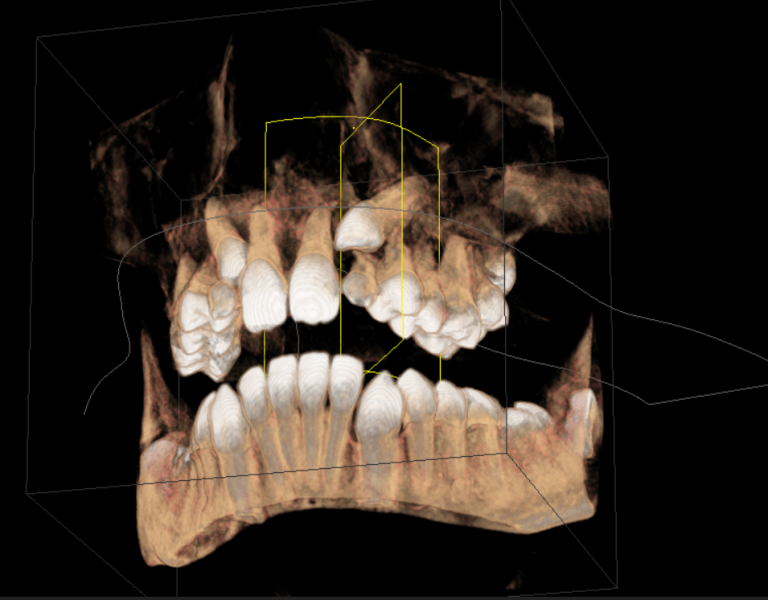

3D-Röntgen in der Kieferorthopädie

Immer häufiger wird in modernen kieferorthopädischen Praxen ein weiteres innovatives diagnostisches Verfahren eingesetzt. Die digitale (dentale) Volumentomographie (DVT) dient der dreidimensionalen Darstellung der Zähne im Kieferknochen. Sie kommt mit einer vergleichsweise geringen Strahlenbelastung aus.

Die Anwendung der DVT ist auf den Kopfbereich beschränkt. Deshalb wird sie ausschließlich im Bereich der Zahnmedizin, der Mund-, Kiefer- und Gesichtschirurgie sowie im HNO-Bereich eingesetzt. Die DVT-Aufnahmen eignen sich hervorragend zur Lageanalyse von verlagerten Zähnen, bei Asymmetrien oder zur digitalen Therapieplanung. Für die Planung einer Alignertherapie oder computergestützter maßgeschneiderter Bracketsysteme sind sie daher ideal. Dieses relativ neue bildgebende Verfahren gehört aktuell nicht zum Leistungskatalog der gesetzlichen Krankenkassen.